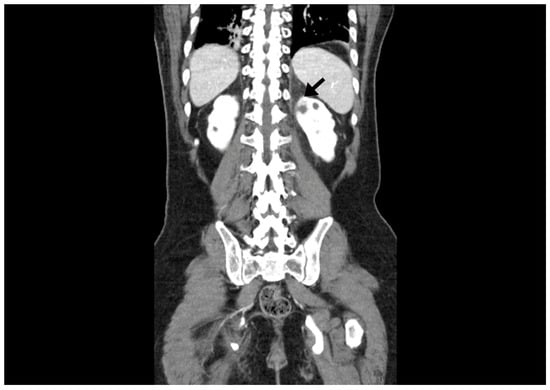

Figure 2. In the abdominal CT, an ill-defined low-density lesion (arrow) at the upper pole of the left kidney is noted.

A 34-year-old man with cerebral palsy presented with high fever (39.5 °C), left flank pain for 3 days, and gross hematuria. Twenty years prior, he underwent a ureteroscopic stone removal and ureteral dilation at another hospital and had intermittent episodes of left renal colic and urinary tract infections. Urinalysis revealed the presence of hematuria (red blood cells: 30–50/HPF), pyuria (white blood cells: >50/HPF), and bacteriuria (bacteria: a few colonies/HPF). The C-reactive protein level was 10.3 mg/dL. An abdominal computed tomography (CT) revealed hydronephrosis with a narrowing of the UPJ (Figure 1). A low-density lesion of approximately 1.6 cm with subtle irregular margins in the upper pole of the left kidney, suspected to be a renal abscess, was observed (Figure 2). Urine cytology examinations were performed three times, but all were negative. After 3 days of parenteral antibiotic treatment, the patient became afebrile. The follow-up urinalysis results were normal. A follow-up CT, performed 3 months later, showed that the ill-defined low-density lesion at the upper pole of the left kidney had disappeared. hydronephrosis with a proximal ureteral narrowing was suggestive of ureteral UPJO associated with an improved state of combined ureteritis and a renal abscess. Suspecting recurrent left pyelonephritis due to the UPJO, laparoscopic pyeloplasty was planned. Prior to the pyeloplasty, the patient underwent retrograde pyelography (RGP). The RGP revealed a dilated left renal pelvis and the abrupt narrowing of the UPJ, and there was no filling defect in the left urinary tract. The surgery was performed using a transperitoneal approach. The laparoscopy revealed a UPJO (Figure 3). The dismembered technique was used for the reconstruction of the UPJ. The surgery was completed without complications. A pathological examination revealed that the excised stenotic segment had a UC with an invasion beyond the muscularis propria into the periureteral fat. This pathological stage was pT3, and the grade was high (World Health Organization (WHO) grade 3). Due to the possibility of residual cancer in the remaining ureter, we decided to perform a laparoscopic radical nephroureterectomy with a bladder cuff excision. Two weeks after the laparoscopic pyeloplasty, the patient underwent a second surgery. A pathological examination revealed residual tumor cells in the proximal ureter. The tumor invaded the subepithelial connective tissue (rpT1). The final pathological stage was pT3 with a high grade (WHO grade 3). There was a multifocal urothelial carcinoma in situ in the renal pelvis and mid-ureter. Postoperatively, the patient received four cycles of adjuvant chemotherapy with gemcitabine and cisplatin. The patient has been undergoing regular follow-up sessions without evidence of a recurrence or distant metastasis for 2 years.